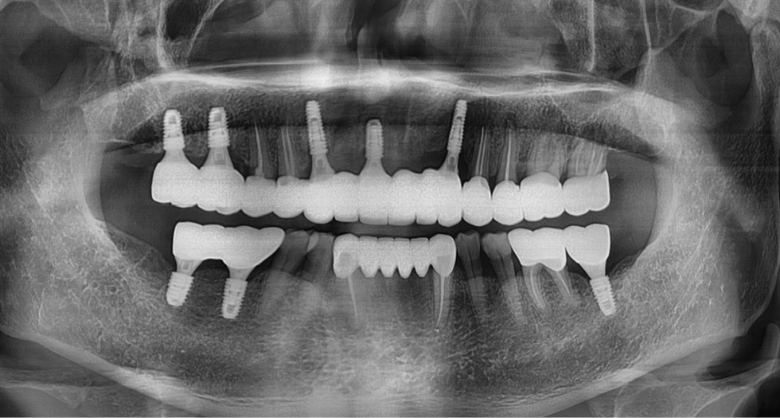

역삼동임플란트 저희 뉴엔은 컴퓨터로

분석하여 임플란트 수술을 진행하고 있기 때문에

보다 안정적이며 명확하게 그리고

신속한 수술이 가능합니다.

1차 수술은 부분 마취 후에 치근에 해당되는

인공 치근을 골 내에 이식하는 과정으로

잇몸을 절개하고 골조직을 노출시킨 다음

인공 치근을 삽입한 후에 잇몸을 봉합합니다.

이 과정에서 손상을 가능한 한 적게 진행합니다.

2차 수술은 1차 수술한 부위를 절개하여 나사를

노출시킨 다음 기둥을 연결하고 상부 보철

치아 제작을 위한 본을 뜹니다. 최적의 보철물

디자인으로 제작해야 보철물의 모양이

위생 관리가 용이하게 제작됩니다.

다음으로 상부 보철물의 종류에 따라

치과용 시멘트나 연결 나사로 고정시킵니다.

이후 교합 조정을 하는데 이는 맞물리는 반대

치아와의 접촉을 원활히 하는 과정입니다.